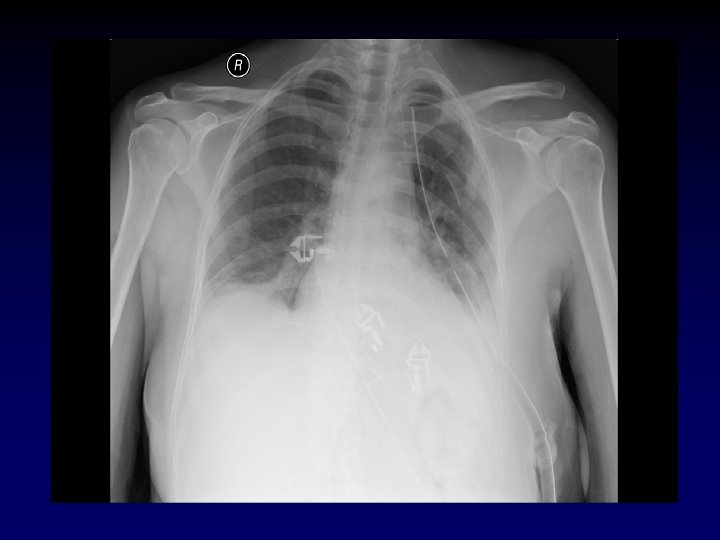

Tube Thoracostomy • Indications: − Hemothorax/Pleural effusion − Pneumothorax − Note for tension pneumothorax first tx should be 14 or 16 gauge angiocath in 2 nd intercostal space in midclavicular line. • Anatomy: • 5 th intercostal space in the anterior axillary line (at the level of the nipple). • Measure tube from insertion site to apex of lung.

Tube Thoracostomy • Procedure: − Prep and drape hemothorax − Infiltrate skin, subcutaneous tissue and pleura with 1% lidocaine – – 1. 5 -2 cm incision directly over the 6 th rib down to the rib With a blunt clamp, dissect over the superior edge of the rib. Bluntly pierce the pleura with the clamp and spread the track. Be prepared for a rush of blood, fluid and/or air.

Tube Thoracostomy • Procedure (cont) – Place finger in track to confirm intrapleural positioning and lyse any adhesions. – Insert tube via track (with or without clamp) towards apex of lung. – Attach tube to pleuravac. – Secure tube to patient with heavy silk suture and tape all connections.

Warning! • History of chest tubes, thoracotomies or inflammatory pulmonary pathology. – Assume adhesions between the lung and the chest wall. – The chest tube insertion cause a lung laceration. • Be very careful how low you are, you can easily place an abdominal tube if you are not careful.